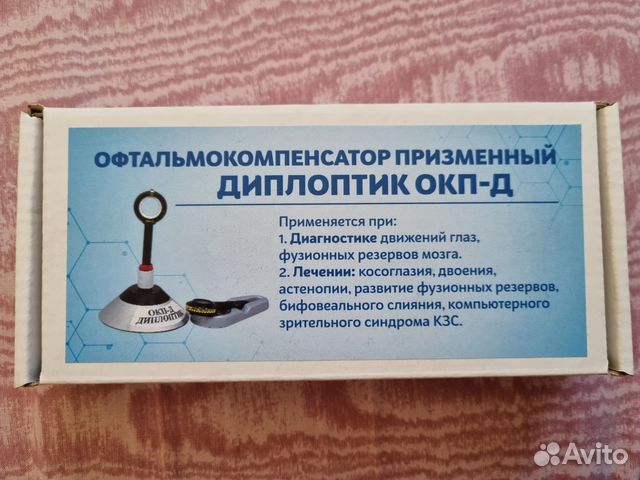

Диплопия: механизм развития и методы лечения

Раздел: Картинки жизни